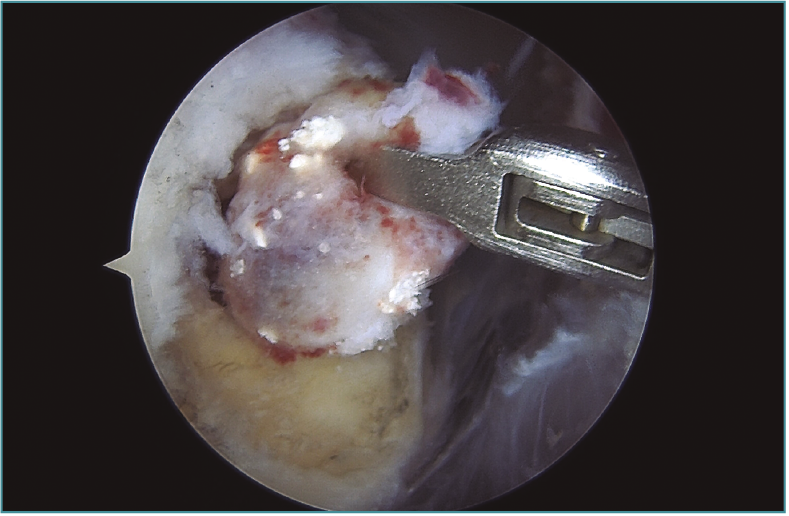

Imagen de artroscopia de hombro en la que se observa la extracción del contenido (estudio anatomopatológico: tejido colágeno denso con calcificaciones y osificación focal) de una expansión intraósea en la tuberosidad mayor del húmero de una tendinitis calcificante del supraespinoso.